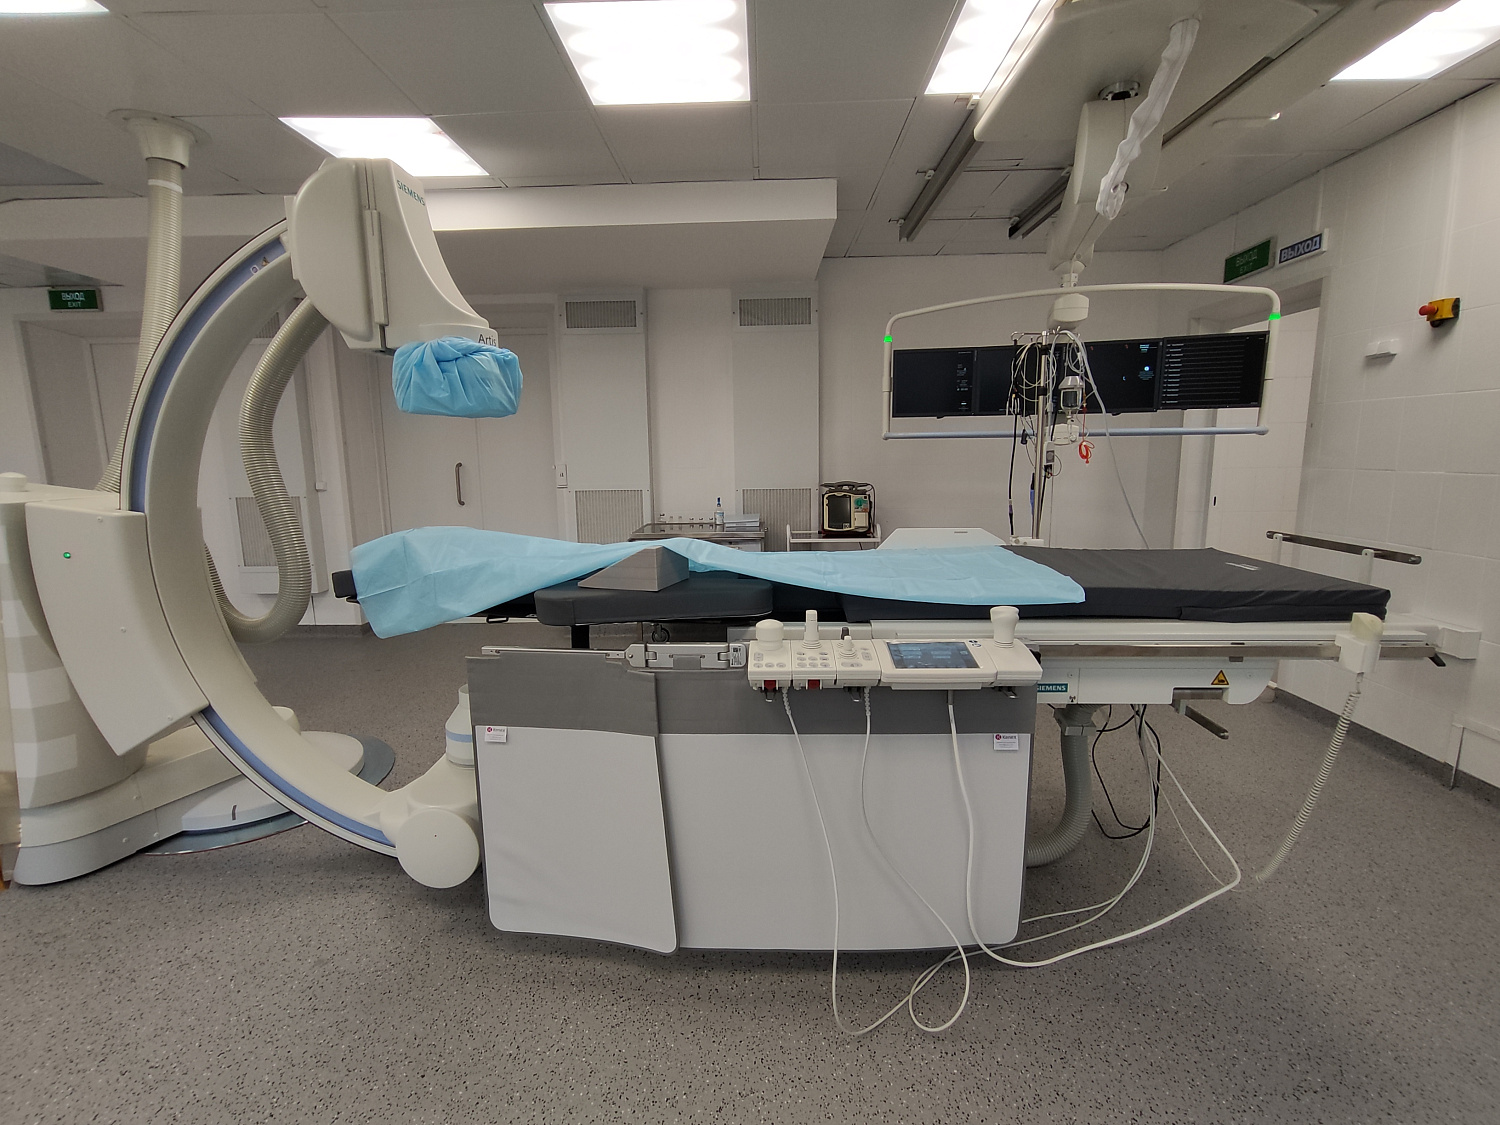

В Областном клиническом кардиологическом диспансере прошли рентгенохирургические вмешательства на новом ангиографическом комплексе «Artis zee floor». Он установлен и введен в эксплуатацию в клинике кардиологии ГУЗ «ОККД» в рамках федеральной программы «Борьба с сердечно-сосудистыми заболеваниями» нацпроекта «Здравоохранение».

Новое оборудование представляет собой высокотехнологичный комплекс, с помощью которого под воздействием рентгеновского излучения можно визуализировать просвет сосудов, полостей сердца и кровоток. Это позволяет врачам выявлять такие патологии, как закупорки, сужения сосудов, тромбы, аневризмы, оценивать целостность и структуру сосудистой стенки и мн.др. На основе полученных данных можно максимально точно поставить диагноз, определить локализацию и характер поражения, а также спланировать и провести дальнейшее лечение, включая малотравматичное хирургическое вмешательство.

Ежегодно в ОККД проводится более 2,5 тыс. эндоваскулярных вмешательств при ишемической болезни сердца, более 6 тыс. диагностических исследований и порядка 1,5 тыс. операций при различных формах нарушения ритма. Данный ангиографический комплекс стал четвертым по счету в арсенале врачей кардиодиспансера.

«Его установка позволит нашему учреждению увеличить объем и повысить качество оказываемой плановой и экстренной высокотехнологичной медицинской помощи пациентам с острым коронарным синдромом, нарушениями ритма сердца и другими болезнями сердечно-сосудистой системы, а также для проведения диагностических процедур», - прокомментировал исполняющий обязанности главного врача ГУЗ «ОККД», д.м.н. Сергей Николаевич Толстов.